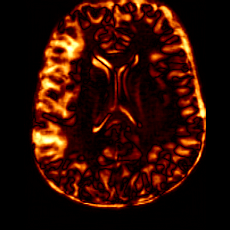

Figure 7: Ablation study of Lesion Consistency Guidance (LCG). Without LCG, the generated pathological regions are indistinct and show weak pathological expression in both examples.

Lesion Consistency Guidance. Fig. 7 illustrates the impact of Lesion Consistency Guidance (LCG) for healthy-to-pathology editing. Without LCG, the generated lesion regions appear blurry around lesion boundaries, and the pathological patterns are less distinct, resulting in ambiguous lesion localization and weak pathological expression. Incorporating LCG produces lesions with more precise localization and well-defined shapes that better align with the given lesion masks, as well as textures and contrasts that exhibit stronger pathological characteristics. These results demonstrate that LCG effectively enforces lesion-aware conditioning, enhancing both spatial and semantic consistency of the generated pathological regions.